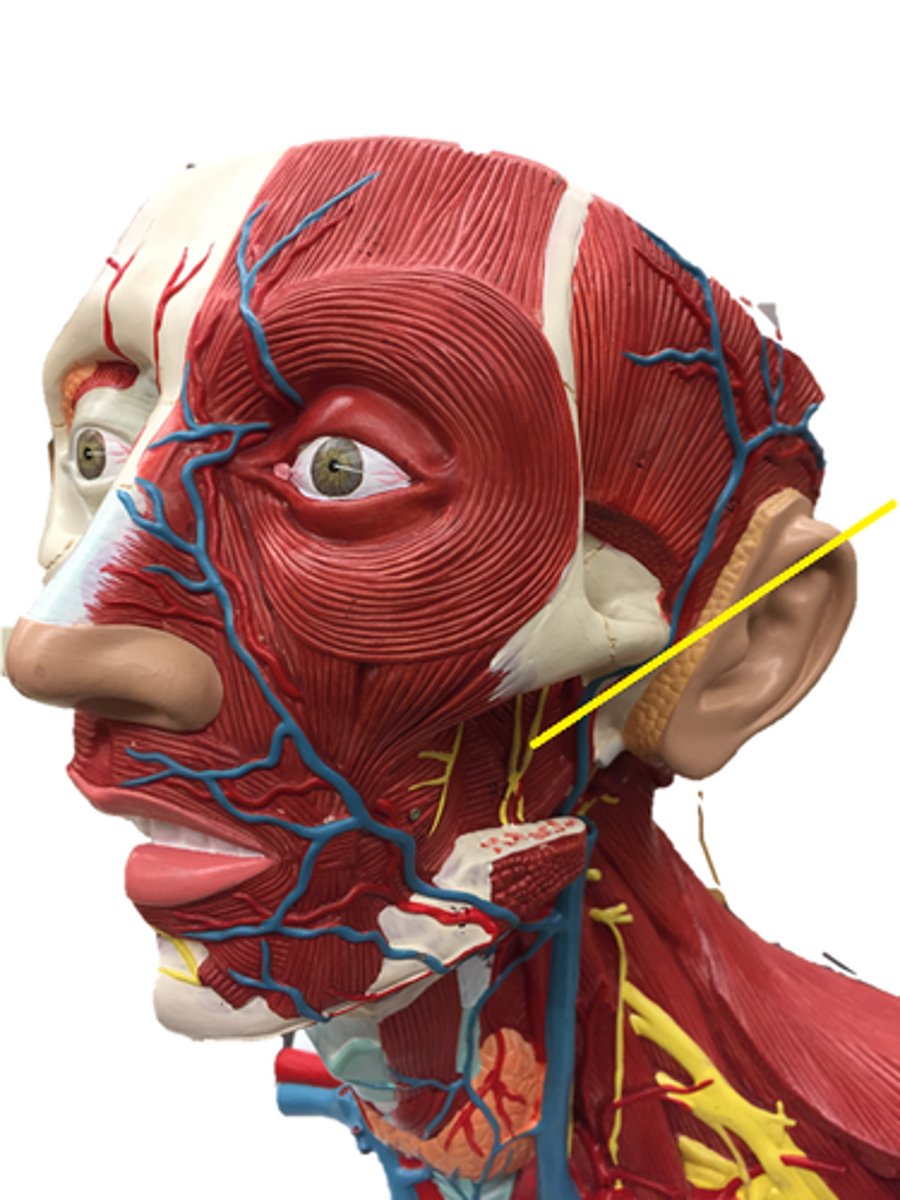

trigeminal nerve

inferior alveolar nerve

facial nerve

infraorbital nerve

maxillary nerve (V2)

Buccal nerve